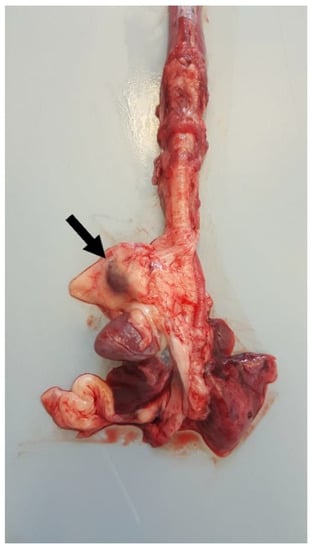

Chest and abdomen radiograms in right lateral and dorsal recumbency revealed a severely enlarged cardiac silhouette, which occupied the thoracic cavity from the third to the tenth pair of ribs, touching the thoracic wall bilaterally. It caused severe dorsal deviation of the trachea, lung, and diaphragmatic compression (Figure 1).

Figure 1. Thoracic radiographs ((A): right-lateral view; (B): ventro-dorsal view). The cardiac silhouette appears severely enlarged, causing dorsal displacement of the trachea and lung and diaphragmatic compression. The microchip transponder is on the left side.